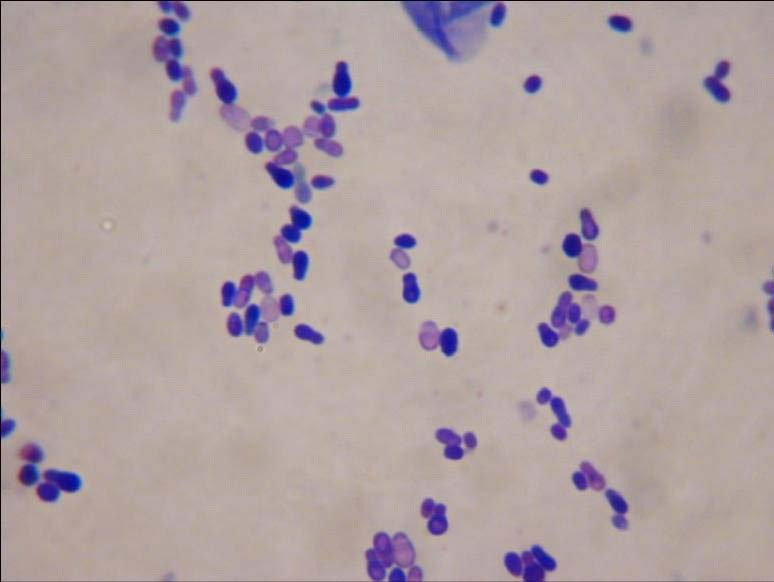

Ear infections under the microscope Franklin Vets

Ear Swabs Technique Interpretation in Vet Medicine